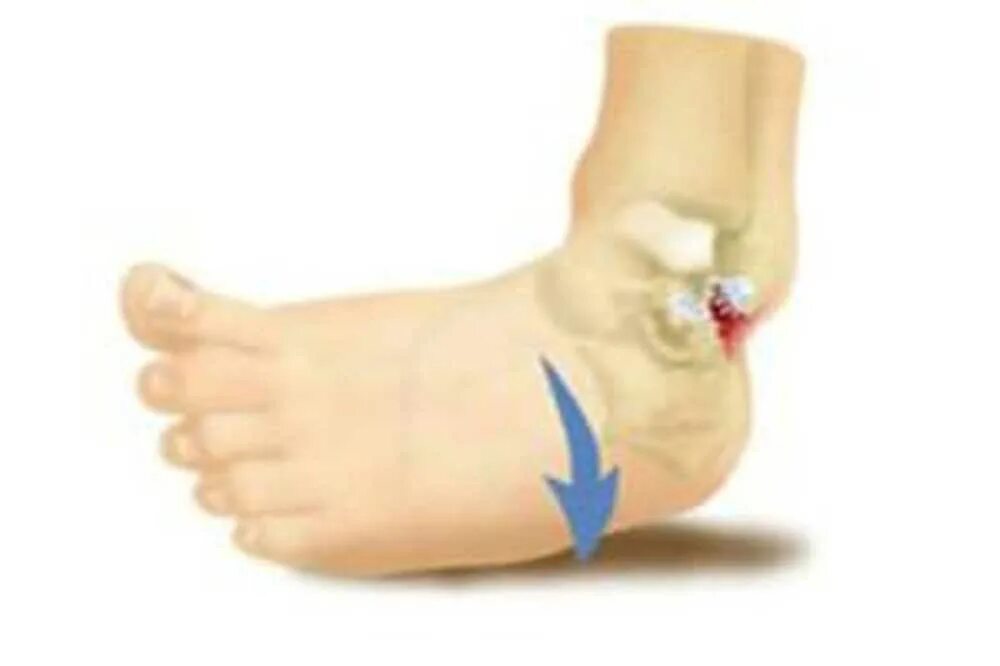

Перелом вывих голеностопного сустава